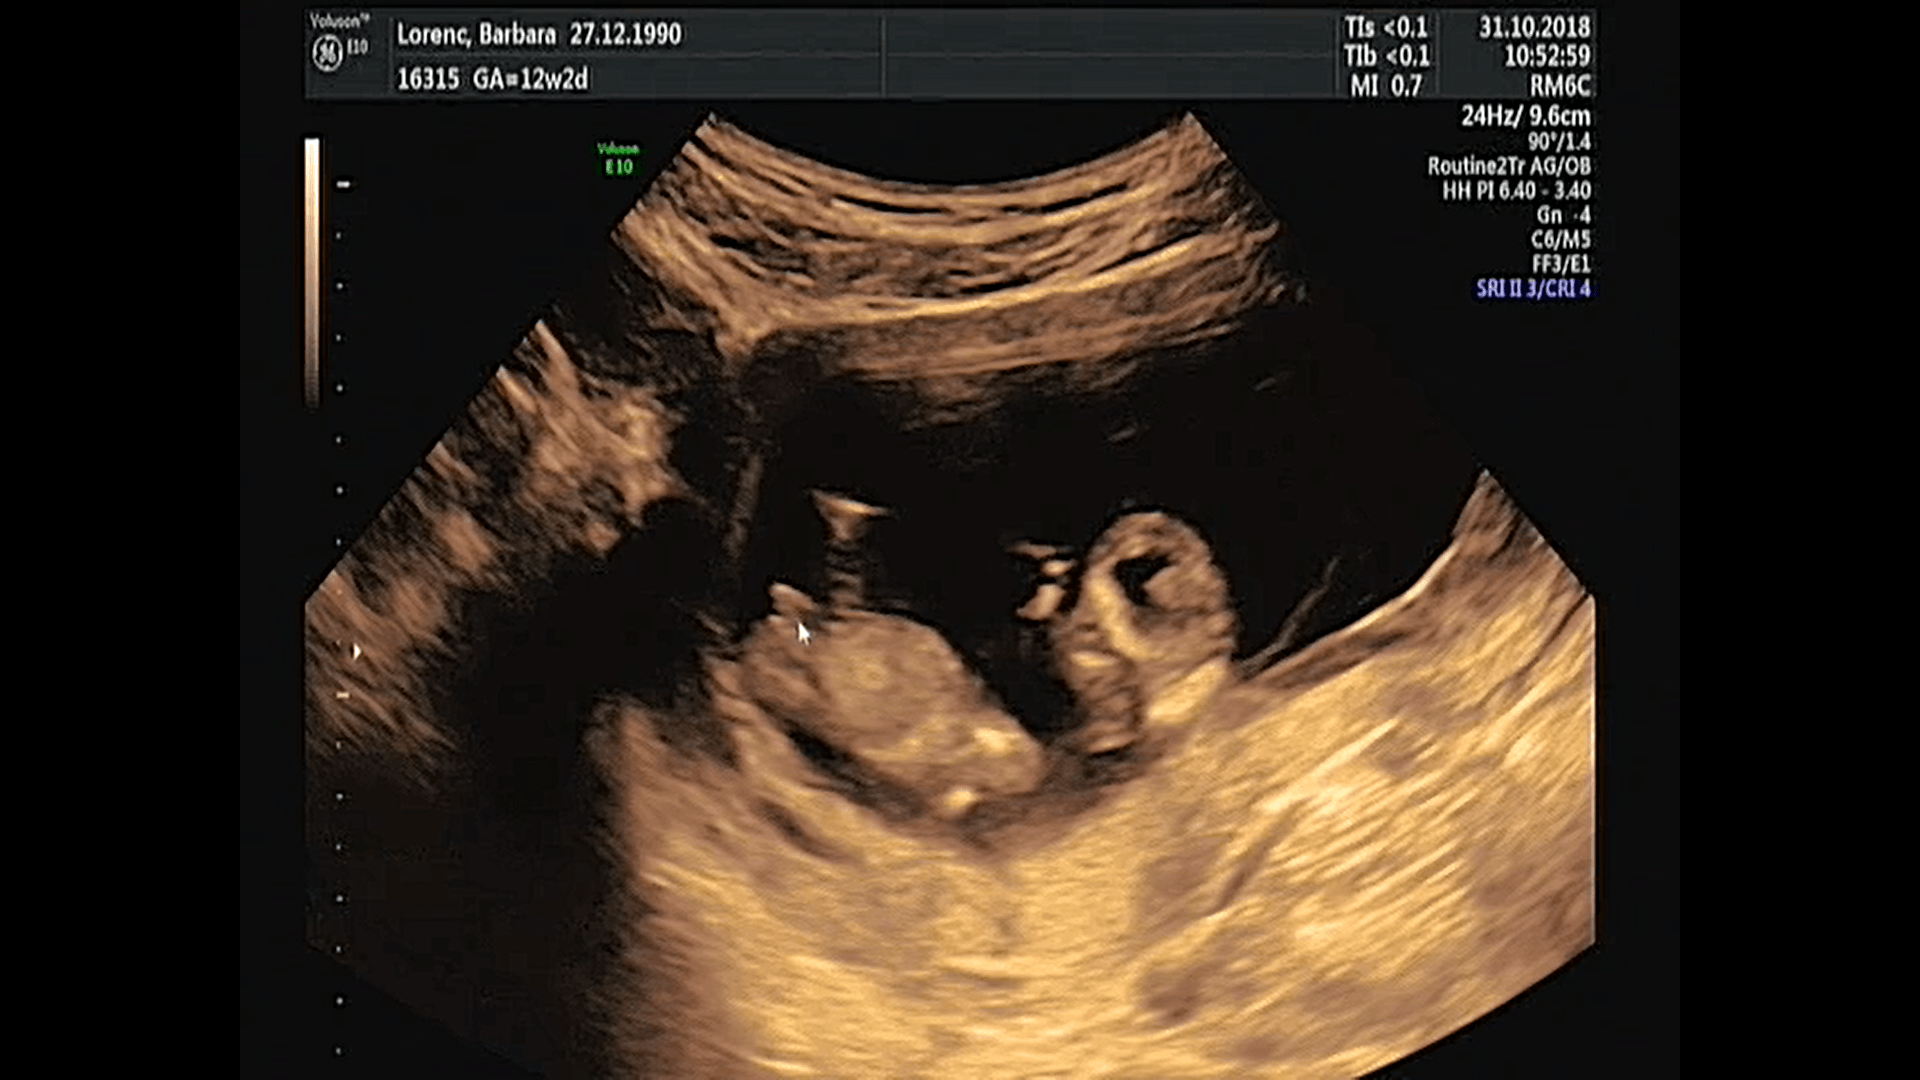

Witam w 19 tygodniu ciąży dowiedziałam się ze będę miała dziewczynkę w 20 tyg okazało się jednak , że to chłopak. Sama już nie wiem bo na jednym usg widać na pewno dziewuche a na drugim chłopca. Może to pempowina ?? Może ktoś mi pomoże rozwiązać ta zagadkę